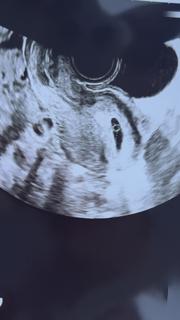

昨日から少し出血があり急遽病院に行ってきました。

8ミリから19.8ミリまで成長していました。卵黄嚢も見えました。

来週には心拍確認できるかな?